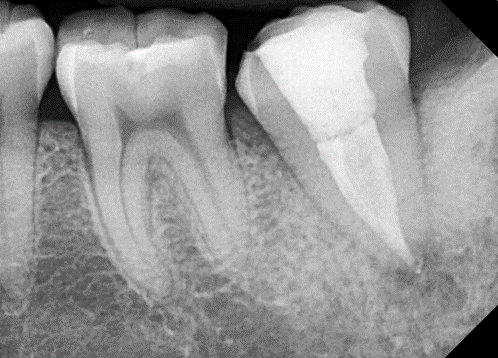

제가 근래에 만난 C형근관을 소개합니다.

![[신경치료] 아래 어금니를 신경치료 할 때 치료할 때 알아야 할 것 (C형근관,고난이도치료) 관련 이미지 8](https://pub-9f2bb3498faf4d1d8714b41df24753e3.r2.dev/content/clinics/archive/nqmm0udu86/naver_blog/honeybeevuvu/assets/by_hash/fcd3afb7ba669bd9ca78c8bc82ee37b3cad75895d59099a1bcd31c0deeb7b1a1.png)

본원의 C형 근관 치료 예시 -20대 여성